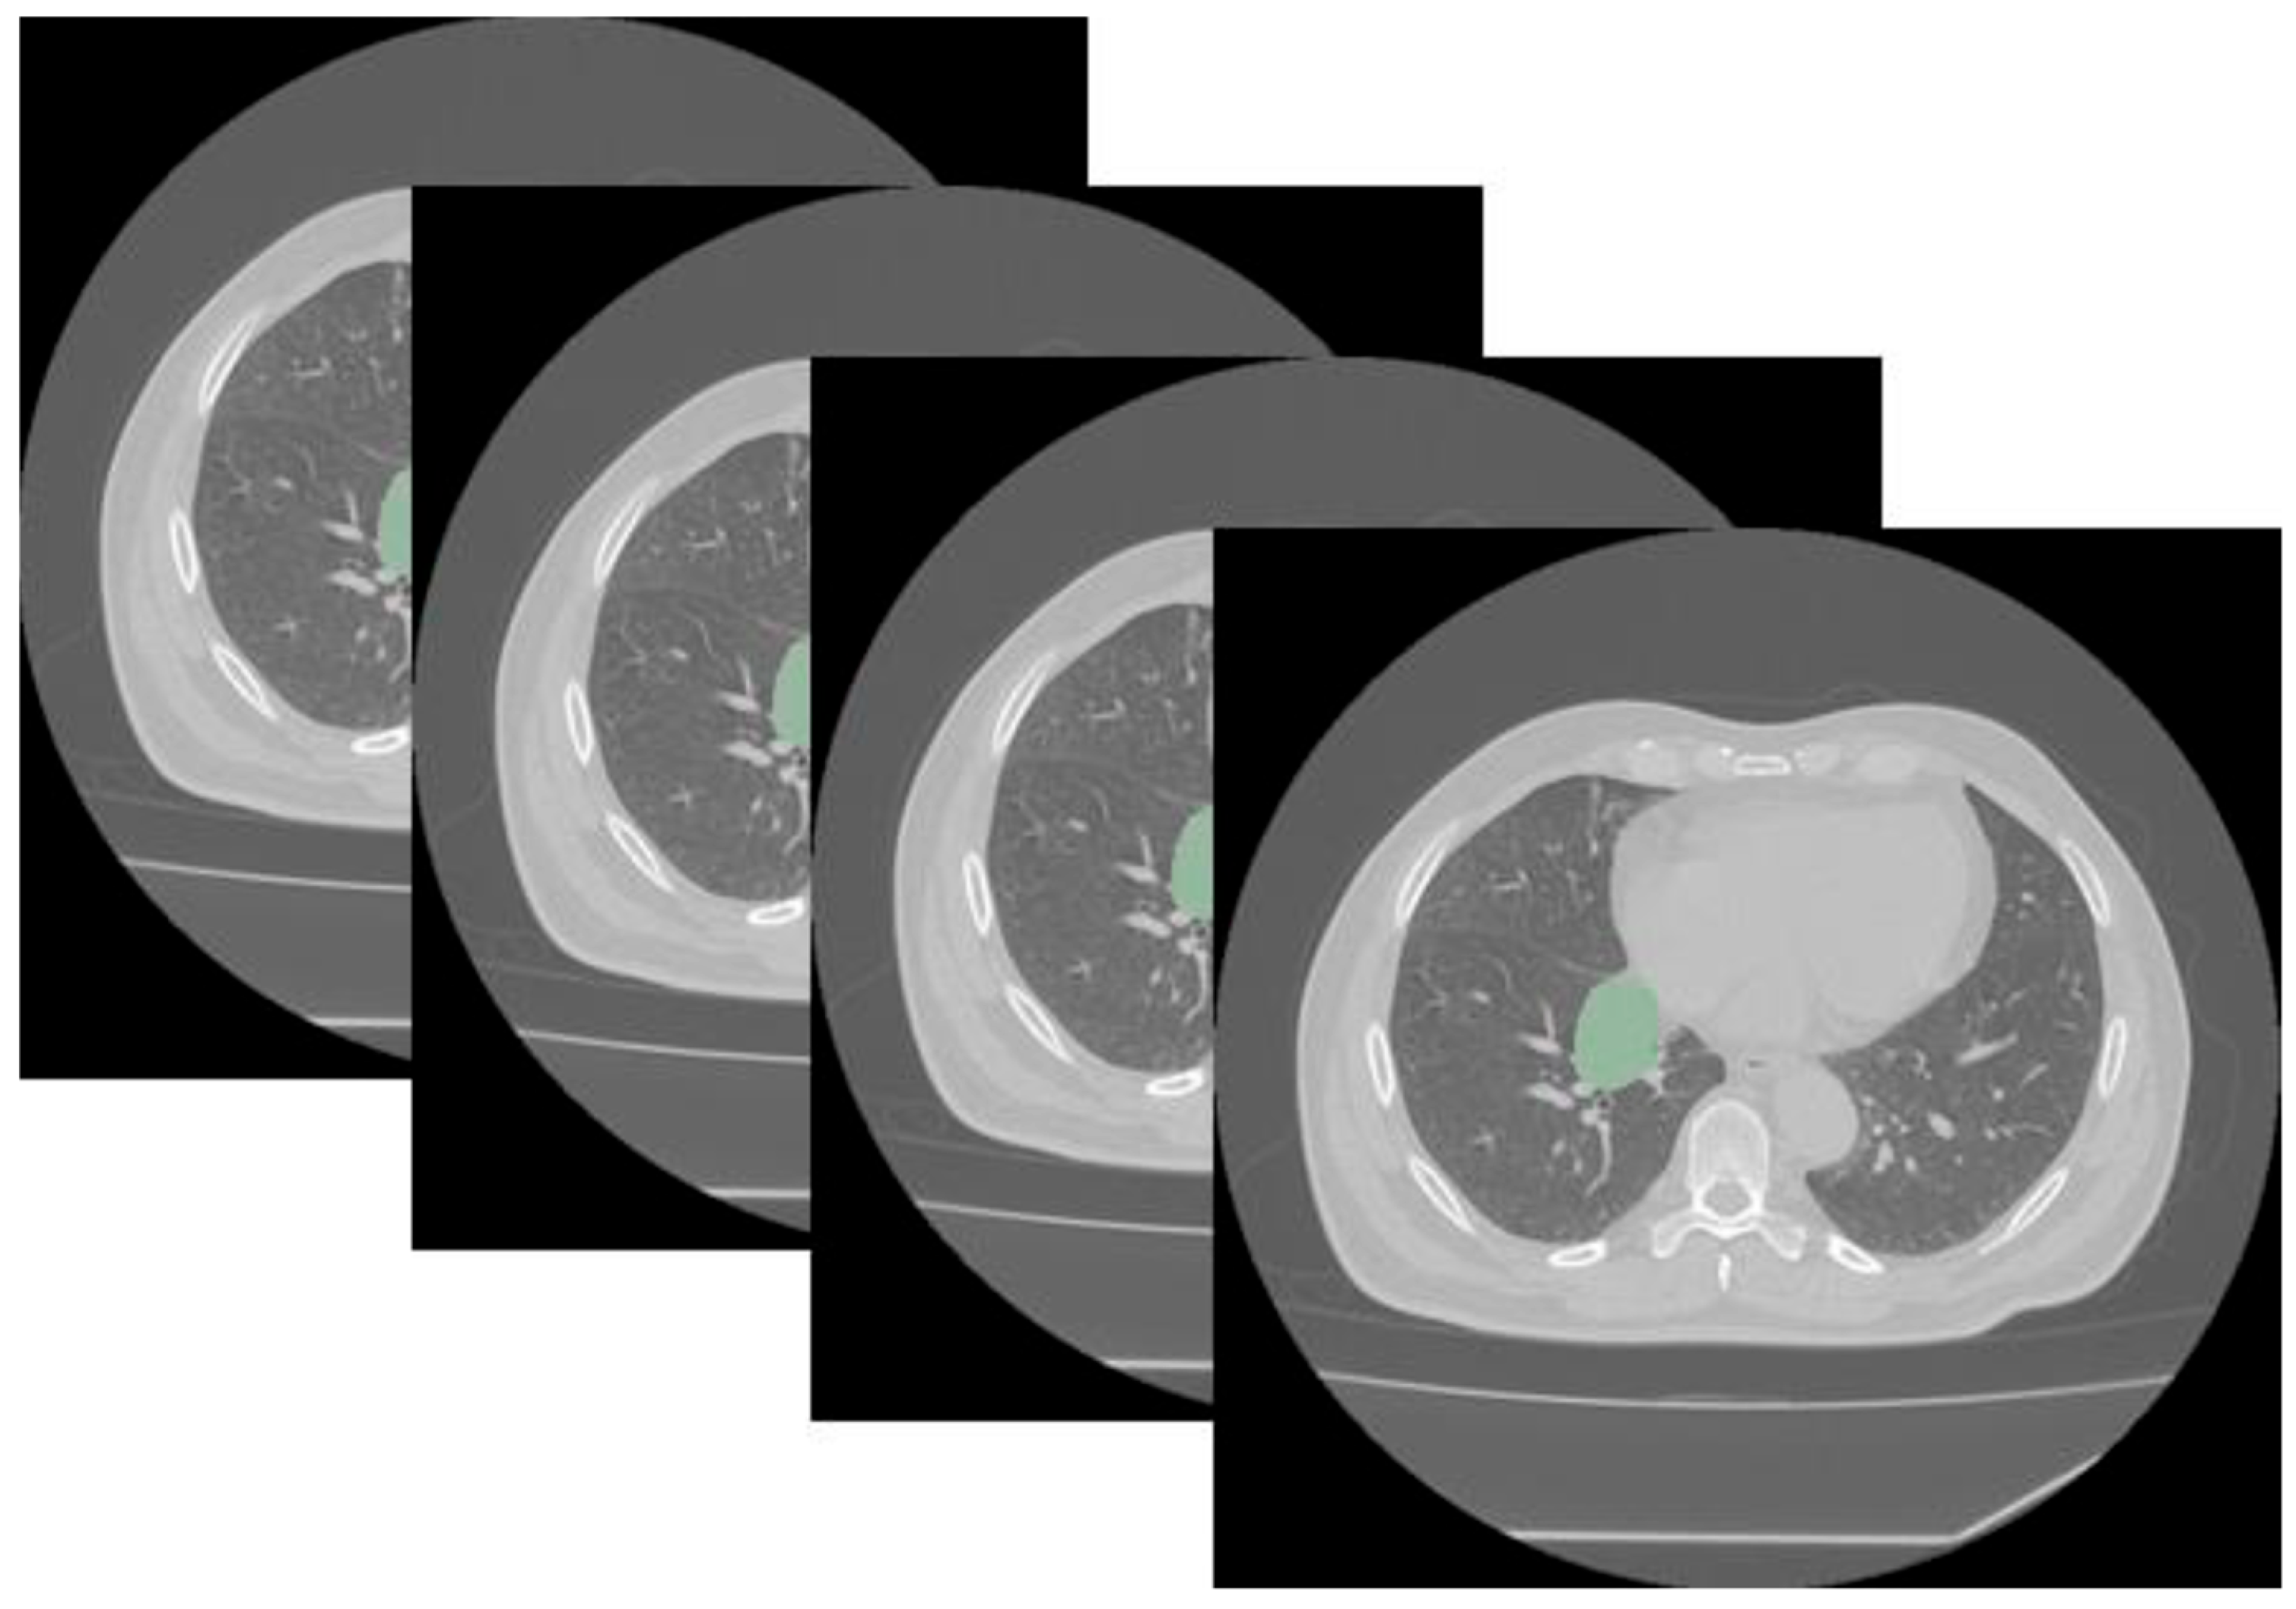

2.3. Tumor Volumetric Segmentation and Radiomic Extraction Characteristics

3.2. Radiomic Analysis